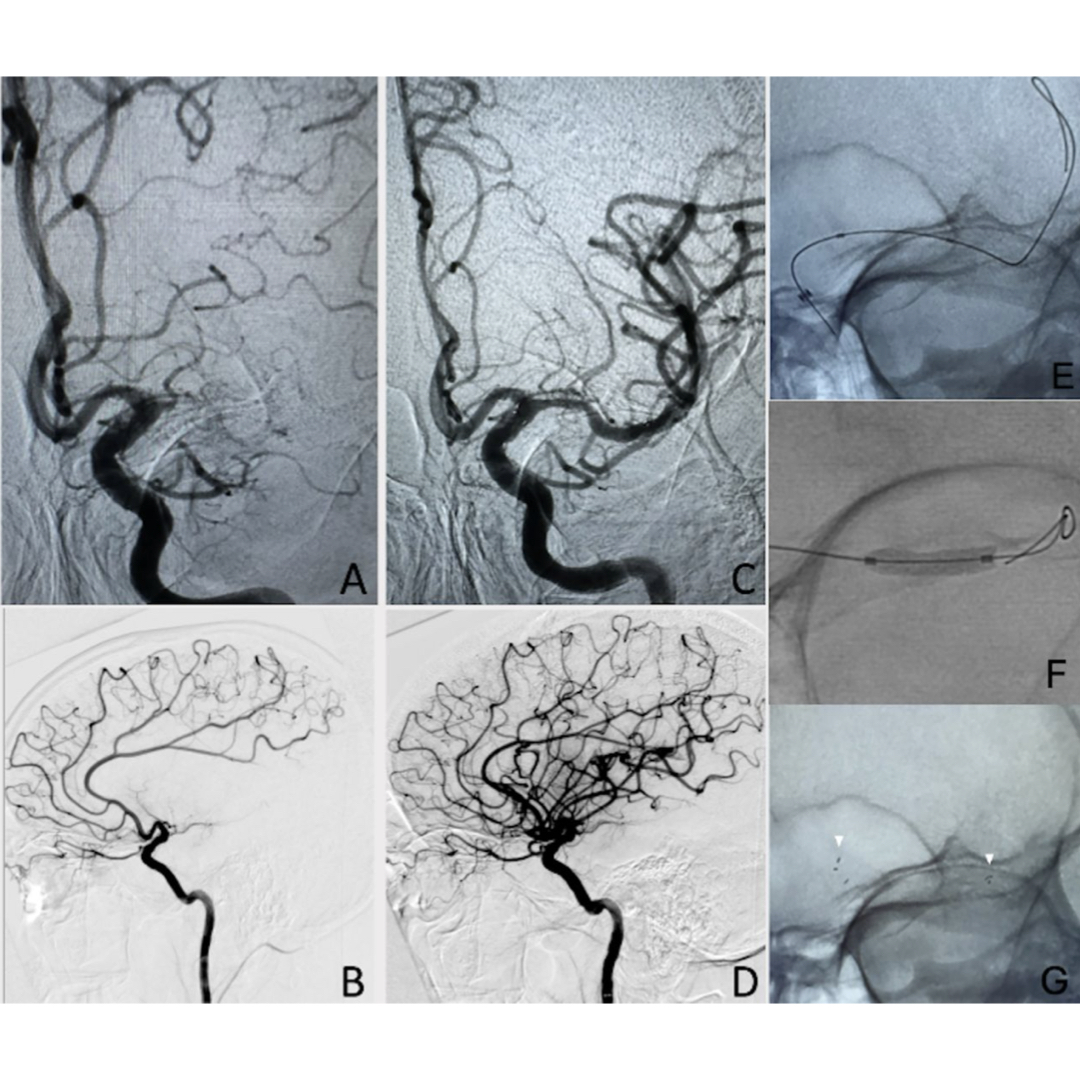

🚨 BREAKTHROUGH IN STROKE CARE! 🚨 A new study shows the feasibility of a single-step technique using the MINI TREK II OTW balloon for deploying the Neuroform Atlas stent in intracranial atherosclerosis-related large vessel occlusions. This method eliminates the need for an

🚨 BREAKTHROUGH IN STROKE CARE! 🚨

A new study shows the feasibility of a single-step technique using the MINI TREK II OTW balloon for deploying the Neuroform Atlas stent in intracranial atherosclerosis-related large vessel occlusions. This method eliminates the need for an